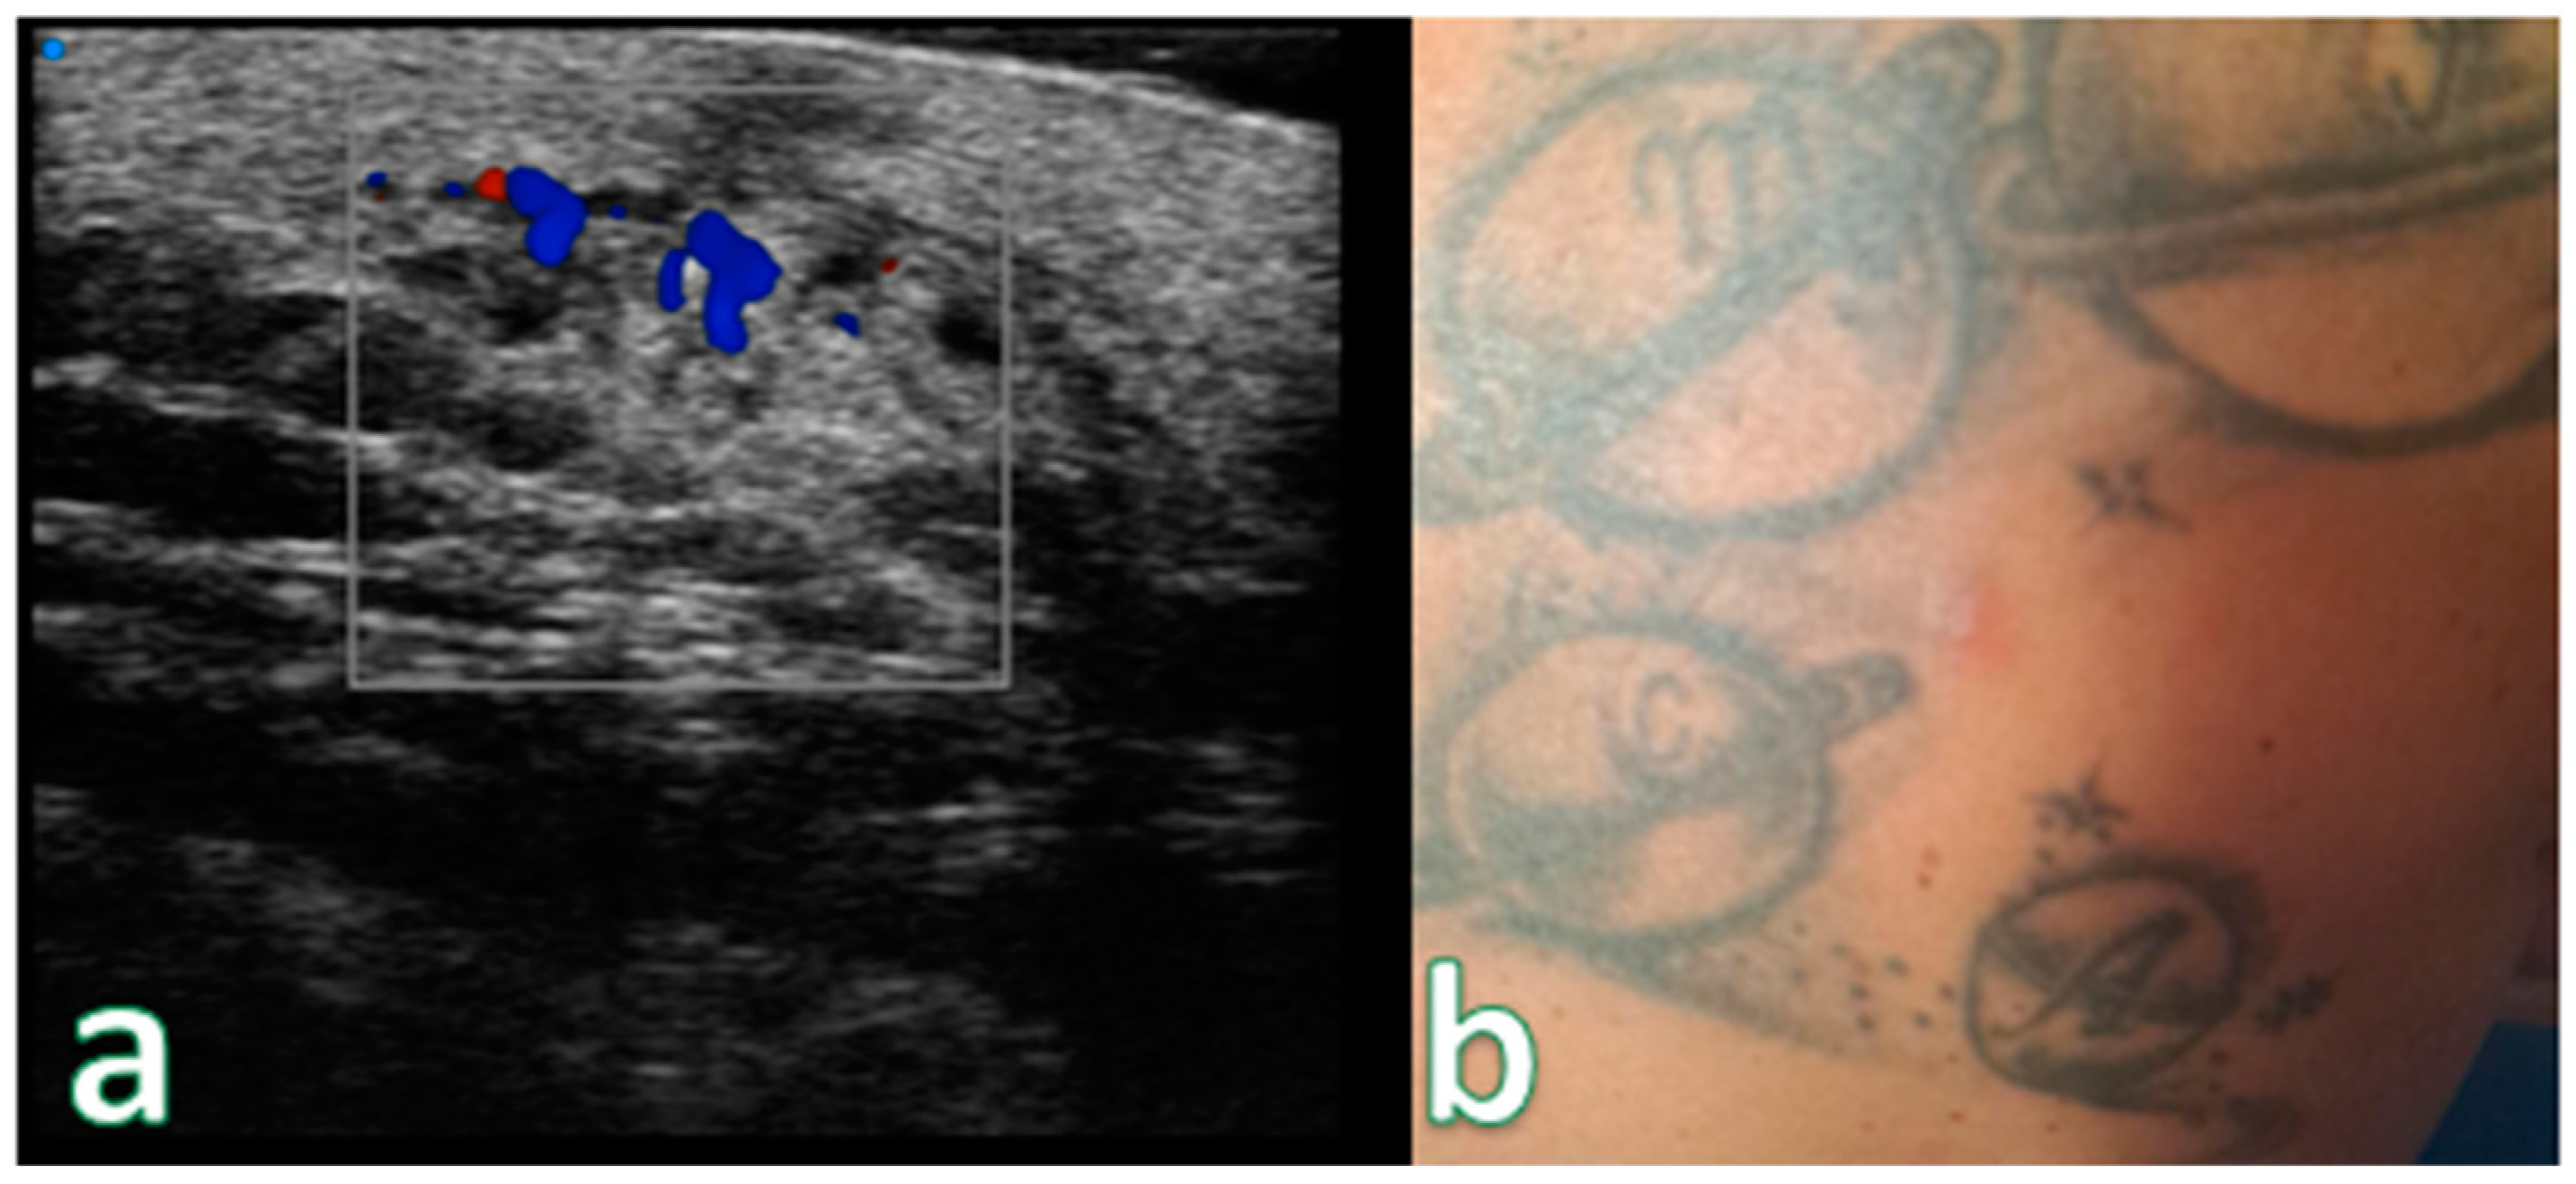

Only two lesions exhibited ulceration, manifested as a gap in the epidermal region with thickening of the surrounding dermis. Cutaneous papules were observed on ultra-high frequency ultrasound (UHFUS) as focal infiltrative lesions, and some of them later coalesced to form ill-defined pseudonodules (Figure 8).

Figure 8. (a) Examination performed with a very high-frequency ultrasound probe at 48 MHz, showing iso-hypoechoic lesions with nodular and multilobulated morphology and irregular margins infiltrating the epidermal and subepidermal tissue at a single point (focal). (b) Reddish, indistinct, slightly exofitic nodule in the lumbar region. Color Doppler analysis showing no significative increase in the signals. Pathological assessment showed B-Cell Lymphoma (recurrence).